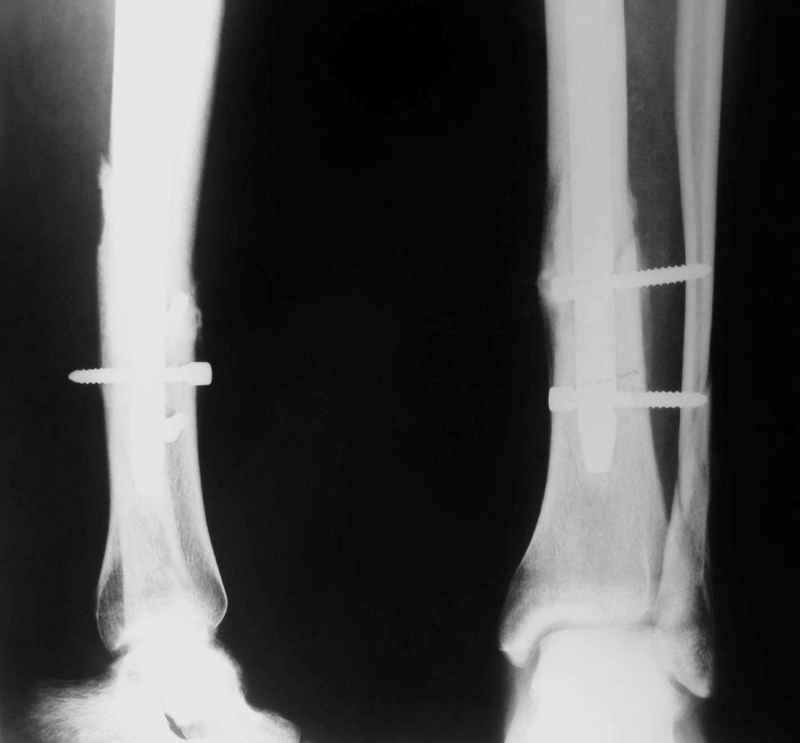

Не удается отправить первичные снимки. А что скажите по имеющимся?!

Отправитель: А. Миронов 21 Январь 2005, 20:49

Уважаемый Валентин!

Выполненный остосинтез нестабилен. Штифт надо заменить по "размеру" на солидный, дистльно три запирающих винта. Успехов!

Отправитель: Alexander Chelnokov 21 Январь 2005, 21:31

Перелом спиральный, то есть низкоэнергетический, так что со сращением дело обстоит уже неплохо, лишь бы "костоеда" не развилась. Отломки выглядят уже стабилизированными костной мозолью, так что довводить винты, наверно, уже незачем. Разве что при клинической оценке подвижность еще есть - тогда можно для стабилизации наложить простейший аппарат, не опасаясь контакта его элементов с гвоздем, поскольку места в дистальном метафизе оставлено более чем достаточно.

Отправитель: Djoldas Kuldjanov, M.D. 21 Январь 2005, 23:48

С Александром согласен, нет необходимости делать дополнительные усилия для сращения, не большая компрессия аппаратом из двух колец и полная нагрузка доделает работу.